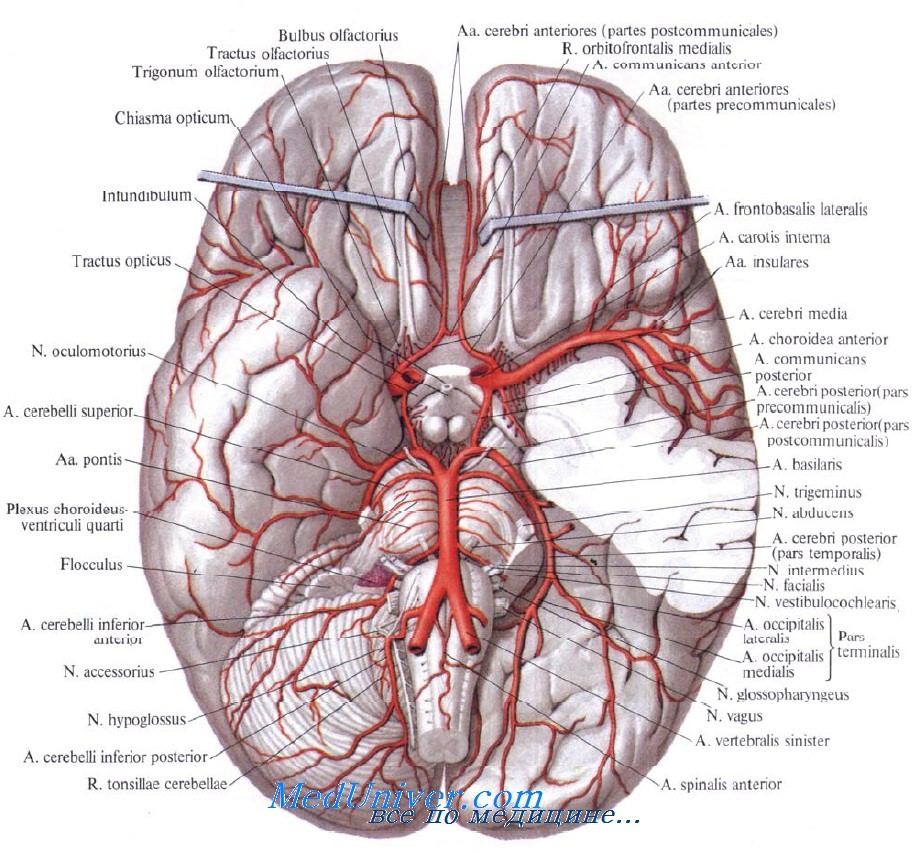

Необычные объекты: Переднее продырявленное вещество

Раздел: Альбом открытий